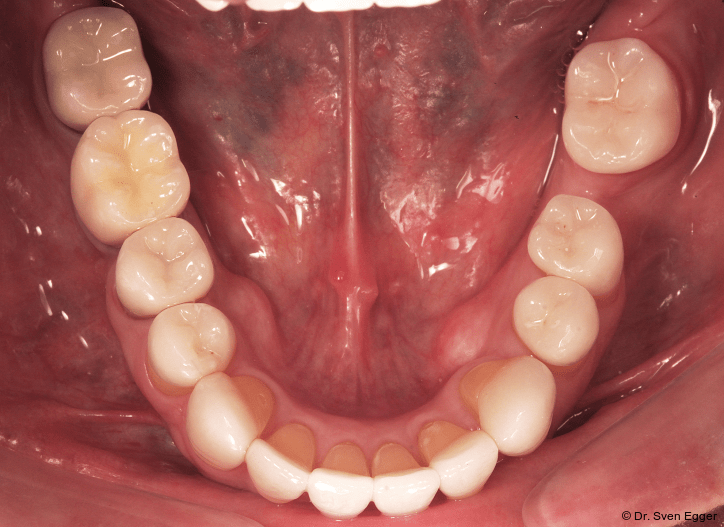

Parodontal zeigen sich keine Auffälligkeiten. Der CMD-Kurzbefund zeigte eine Druckdolenz im Bereich M. masseter und M. temporalis. Die KG sind unauffällig.Die Zähne 17, 26 sind elongiert, 37 ist nach mesial gekippt. Es liegt ein Tiefbiss vor.

Zusammenfassung der ästhetischen Problematik: Es zeigt sich nun hinsichtlich der Länge (Lächeln), Form, Farbe, Stellung der Zähne sowie der rosa Ästhetik ein ansprechendes dentogingivales Erscheinungsbild. Die unteren Frontzähne haben leichten Kontakt auf den Palatinalflächen der oberen Eck- und Schneidezähne. Der Overbite beträgt 4 mm. Der Overjet 2 mm (Abb. 16+17).